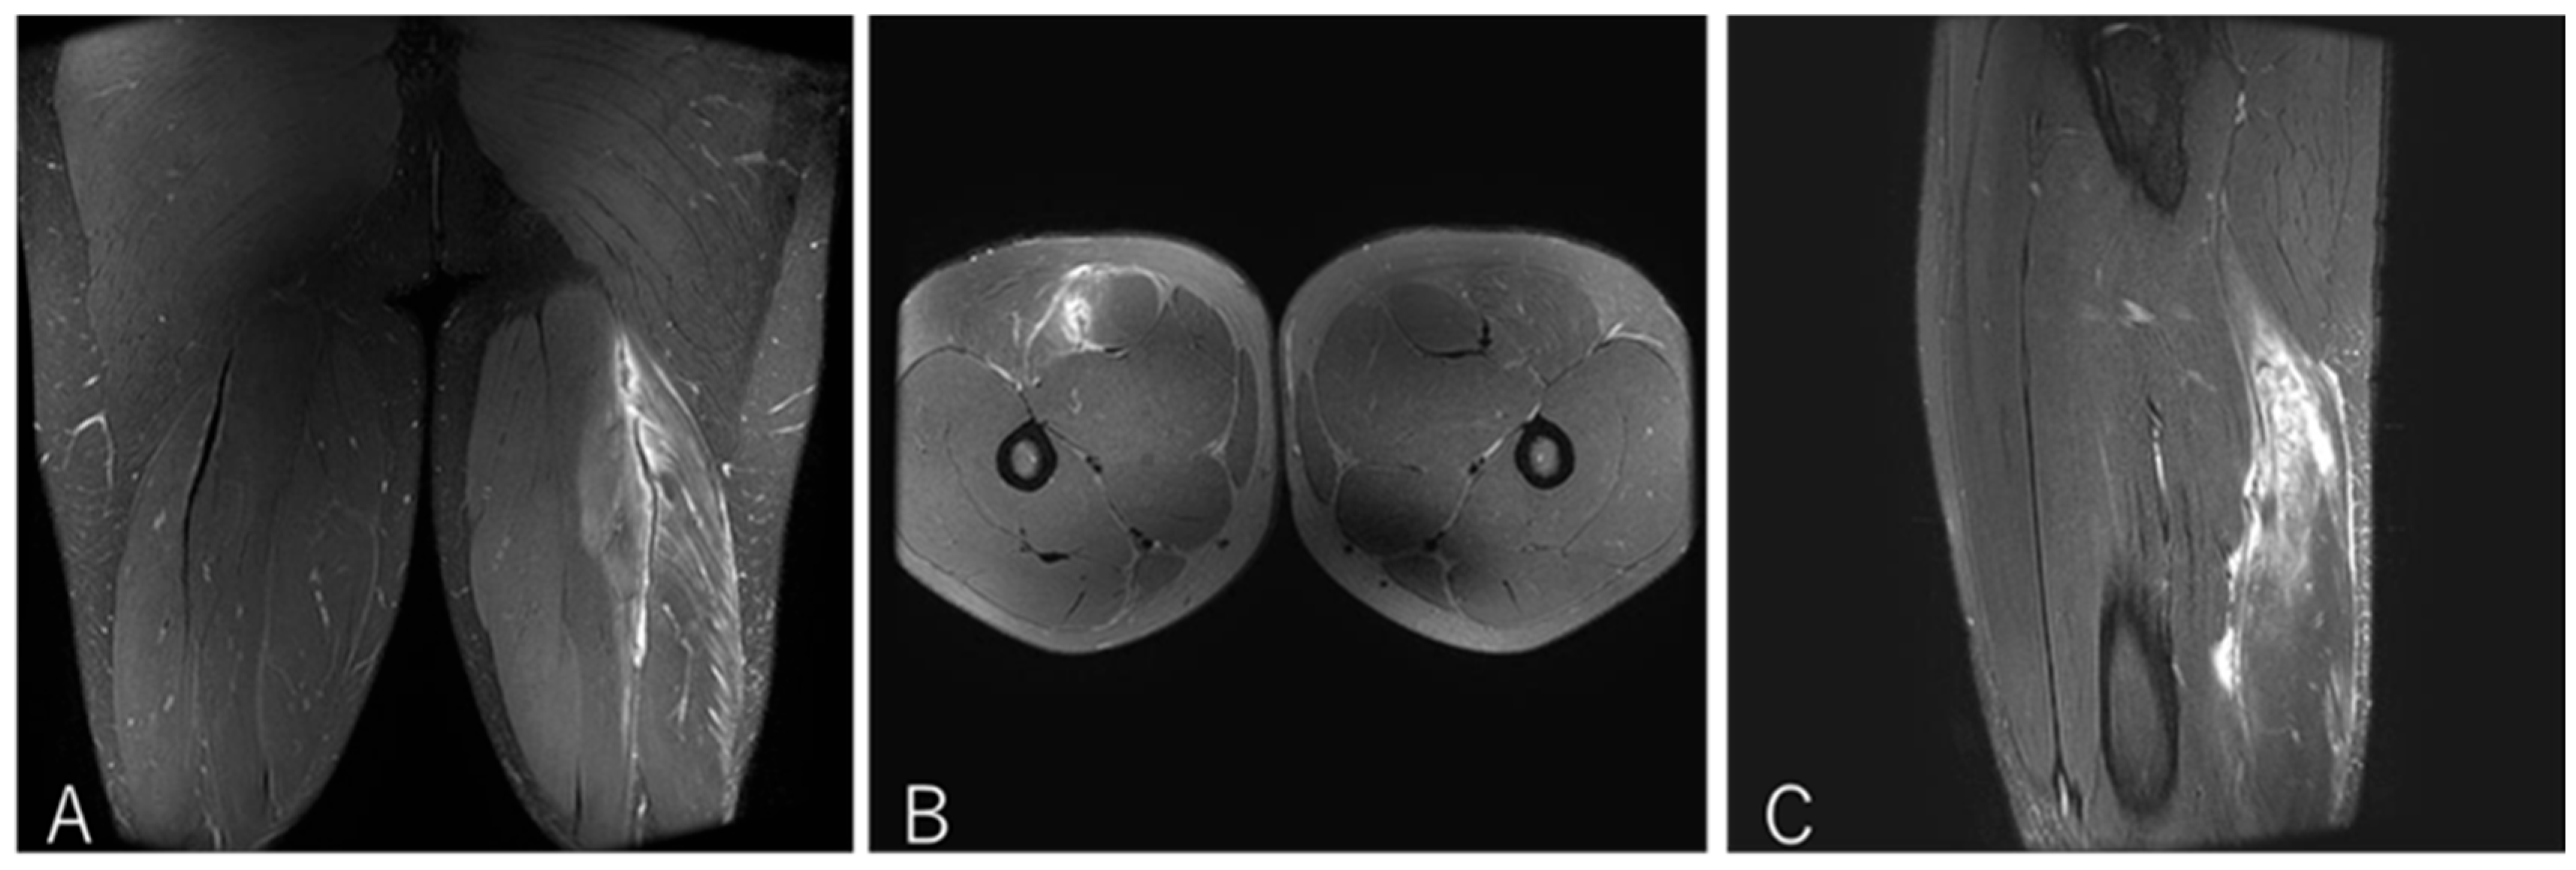

3.4.2. Case 2—Type I/Zone B (Conjoint Tendon Tear), Grade 3

A 20-year-old flanker (FW) experienced sharp twisting pain during a 30 m sprint drill while running at top speed. He returned to play after 14 weeks (Figure 5).

Figure 5. Case 2 MRI images: Conjoint tendon tear, Type I. (A) (Coronal image): Complete rupture of the conjoint tendon (CT). A haematoma is present where part of the CT is not visualised. The MTJ has retracted distally. (B )(Axial image): prone position, A defect on CT and haemorrhage are observed at the rapture site. (C) (Sagittal image): The ruptured distal CT tendon has retracted.